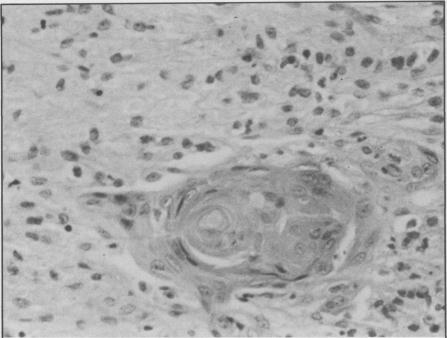

The granular cell myoblastoma (granular cell tumor) is a rare lesion of mesodermal origin that occurs in many areas of the body, including the vulva in seven percent of cases. The exact origin of this tumor is still being investigated. However, nerve cell origin is generally accepted. Lesions of the vulva occur in any age group and must be biopsied to rule out carcinoma, hidradenomas, sebaceous cysts, and papillomas. The recurrence rate of incompletely excised lesions is 25 percent. The microscopic picture of the lesion may simulate carcinoma as a result of reactive hyperplasia of the overlying epidermis. Discovery of a mass on the vulva in any patient which on biopsy reveals a granular cell myoblastoma should lead the examiner to excise the lesion completely and also to search for other lesions at various sites of the body.

颗粒细胞瘤(粒细胞瘤)是一种罕见的中胚层起源病变,可发生于身体的许多部位,其中7%的病例发生于外阴。该肿瘤的确切起源仍在研究中。然而,神经细胞起源已被普遍接受。外阴病变可见于任何年龄组,必须进行活检以排除癌、汗腺腺瘤、皮脂腺囊肿和乳头状瘤。切除不完全的病变复发率为25%。由于上皮过度增生,病变的显微镜图像可能类似癌。任何患者在外阴发现肿块,活检显示为颗粒细胞瘤时,检查者应彻底切除病变,并在身体各个部位寻找其他病变。